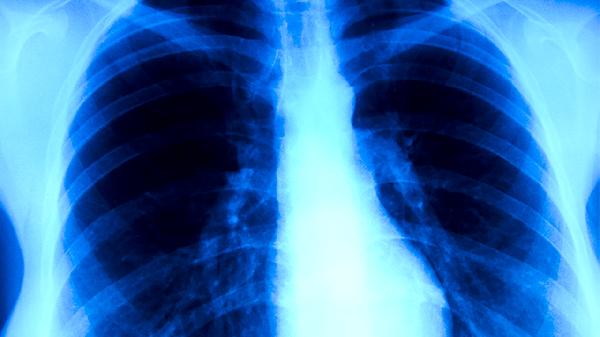

胸闷气促症状显著改善,呼吸频率恢复正常。肺泡充血水肿消退,有效通气面积增加,血氧饱和度提升至95%以上。可进行腹式呼吸训练增强膈肌功能。

恢复期应保持每日1500-2000毫升饮水量,优先选择瘦肉粥、蒸蛋羹等软质食物。进行散步、太极拳等低强度运动,运动时心率控制在220-年龄×50%以下。卧室湿度维持在50%-60%,定期开窗通风。若出现反复发热、痰中带血或呼吸困难加重,需及时复查胸部影像学。